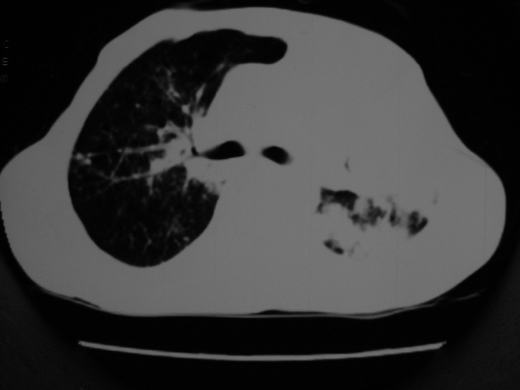

男69岁,年前胸片示肺感染治疗近一月今复查无明显好转,血象正常

双肺内不规则斑点状 片状及结节密实影,部分灶周见索条样影及\"树芽征\",左肺上叶实变,内见充气支气管影及斑状钙化,左侧少量胸腔积液,考虑1)双肺结核2)左侧胸腔积液

右肺多发片絮状结节状及时条索状影,左上肺实变,内可见虫蚀样空洞及支气管气象,左下肺片状及球形病灶,及胸腔积液征象,双肺病灶内多发钙化影,结合病史,考虑双肺继发型肺结核,左胸腔积液

右肺多发片絮状结节状及时条索状影,左上肺实变,内可见虫蚀样空洞及支气管气象,左下肺片状及球形病灶,及胸腔积液征象,双肺病灶内多发钙化影,上纵隔向左侧移位,结合病史,考虑双肺继发型肺结核,左胸腔积液。

右肺多发片絮状、结节状及条索状影,左上肺实变,内可见虫蚀样空洞及支气管气象,左下肺片状及球形病灶,有胸腔积液征象,双肺病灶内多发钙化影,上纵隔向左侧移位,结合病史,考虑双肺继发型肺结核,左胸腔积液。 建议结合ppd检查或纤支镜检查!

双肺结核,左肺实变。左侧胸腔积液(部分包裹)。

右肺可见大片状、云絮状改变。右肺可见散在类圆形影,以外带多见。左肺实变,其内可见明显支气管走行影。纵隔淋巴结有增大,左侧胸腔积液。考虑1、肺结核;2、肺癌肺转移不除外;3、左侧胸腔积液。